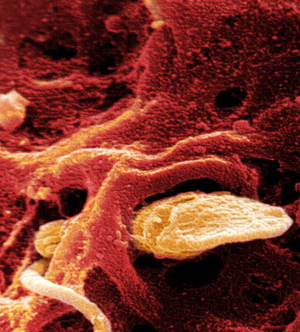

Розмір ембріона в цей час становить усього лише 0,15 міліметрів. Поки ваш малюк являє собою скупчення клітин, як показано на фото на 3 тижні вагітності. Продовжуючи збільшуватися в розмірах, зародок прагнути до матки по маткових трубах.